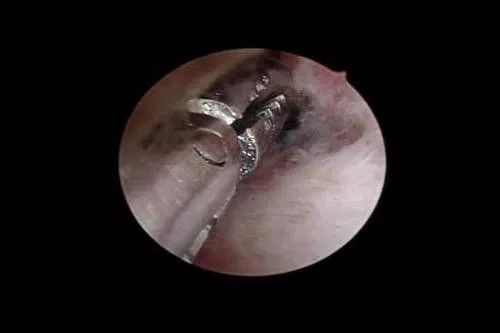

宫腔镜手术是指用宫腔镜进行的微创手术,通过阴道、宫颈口用纤维光源进入宫腔,镜子基本是直的,有的带有角度,但不粗,大约像一次性笔粗细,有放大功能,可以清晰观察子宫腔形态,宫腔内有无息肉、黏膜下肌瘤、有无纵隔或剖腹产切口憩室等,利用微创手术器械进行恢复子宫腔形态或切除息肉等手术。